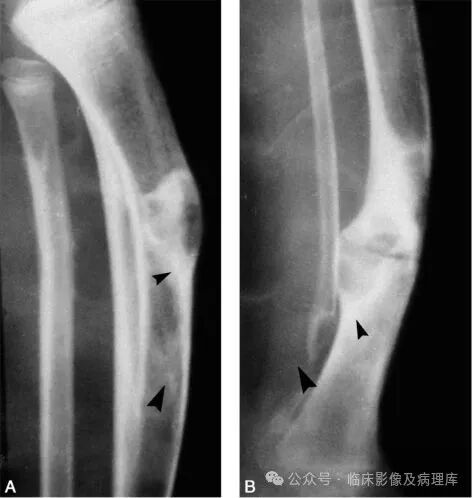

女性,65岁,宫颈癌放疗后。A.骨盆正位片:骨盆诸骨示弥漫性骨质疏松改变,右侧骶骨耳部骨密度减低明显;B.骶骨CT平扫:骶骨弥漫性骨质疏松,双侧骶骨耳部隐见弯曲线样低密度影,周围示片状骨质硬化影。骶骨右前缘示局限性皮质中断;C、D.冠状位SE T1WI和脂肪抑制FSE T2WI示双侧骶骨耳部弯曲线样低信号影,周围见大片状长T1长T2水肿信号;E.核素扫描(后面观):双侧骶骨耳部核素浓聚,以右侧明显